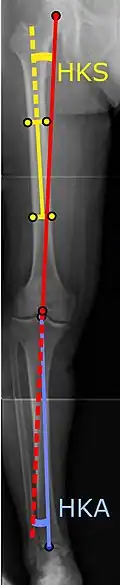

Angles commonly measured before knee replacement surgery: |

To indicate knee replacement in case of osteoarthritis, its radiographic classification and severity of symptoms both should be substantial. Such radiography should consist of weightbearing X-rays of both knees: AP, lateral, and 30 degrees of flexion. AP and lateral views may not show joint space narrowing, but the 30-degree flexion view is most sensitive for narrowing. Full-length projections also are used in order to adjust the prosthesis to provide a neutral angle for the distal lower extremity. Two angles used for this purpose are:

- Hip-knee-shaft angle (HKS),[10] an angle formed between a line through the longitudinal axis of the femoral shaft and its mechanical axis, which is a line from the center of the femoral head to the intercondylar notch of the distal femur.[12]

- Hip-knee-ankle angle (HKA),[11] which is an angle between the femoral mechanical axis and the center of the ankle joint.[12] It is normally between 1.0° and 1.5° of varus in adults.[13]